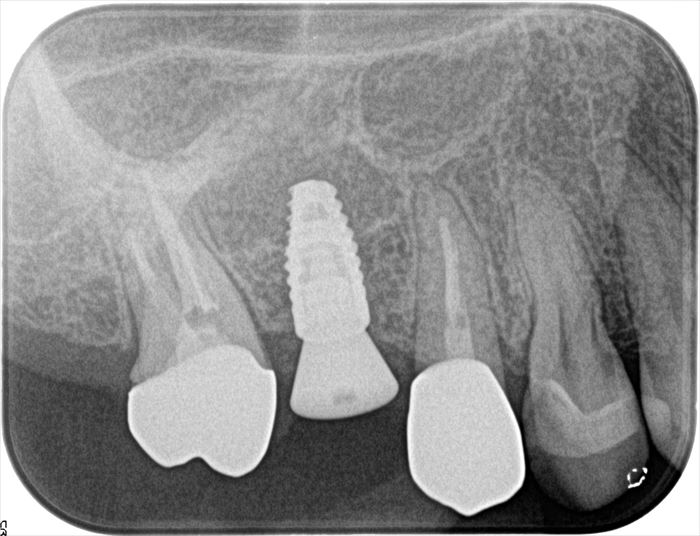

インプラント埋入オペ終了時のデンタルレントゲン写真です。